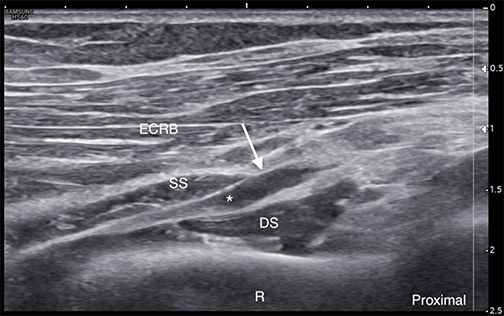

Labeled ultrasound-guided injection at the radial tunnel using a lateral-to-medial short-axis approach, with the needle tip visualized adjacent to the deep motor branch of the radial nerve. * = Deep motor branch of the radial nerve R = Radius Arrowheads = Needle

Labeled long-axis ultrasound image of the deep motor branch of the radial nerve appearing thickened and irregular (arrow) while passing beneath the arcade of Frohse and through the supinator muscle heads. * = Deep motor branch of the radial nerve ECRB = Extensor carpi radialis brevis DS = Supinator muscle deep head SS = Supinator muscle superficial head R = Radius